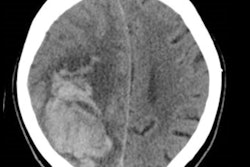

Segmentation of regions of interest on the CT exams was performed on the ITK-Snap 3D image segmentation software. Radiomics features -- including 1,106 first-order, texture, shape, and wavelet features -- were then extracted with the open-source pyradiomics software.

The best-performing model used LASSO for feature selection followed by logistic regression for classification. LASSO selected seven optimal radiomics features for analysis, including six texture features.

Four clinical features -- initial hematoma volume, diastolic blood pressure, satellite sign, and blend sign -- were significantly associated with hematoma expansion (p < 0.05).